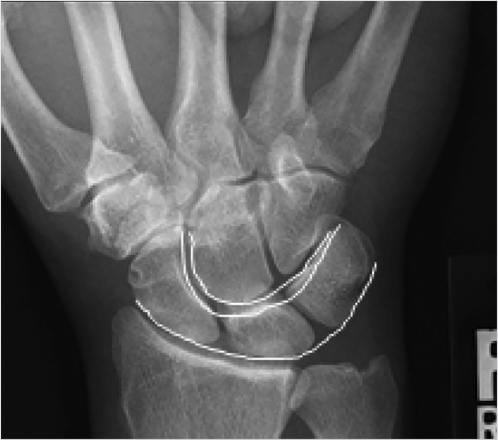

When evaluating for bone or ligament injuries to the wrist, four X-ray views of the wrist are needed: posteroanterior (PA), lateral, scaphoid (PA in ulnar deviation), and 45 degree semipronated oblique. A PA view of the wrist should show three smooth radiographic arcs, known as Gilula’s lines (Fig. 2‑3). Bone articulations normally have apposing parallel surfaces separated by 2 mm or less. A step off or discontinuity of Gilula’s lines, carpal overlap, or unusually wide distances between bones suggests an injury. A normal lateral view shows the radius, lunate, capitate, and third metacarpal lined up vertically. Angles frequently used to evaluate carpal stability are the capitolunate, scapholunate, and radiolunate angles, based on the lateral view (Fig. 2‑4). The capitolunate angle is measured by drawing a line perpendicular through a line connecting the palmar and dorsal tips of the lunate. This is compared to the capitate axis. The normal capitolunate (CL) axis is 0 ± 15 degrees. The scaphoid is represented by a line that connects the two proximal and distal convexities of the palmar aspect of the bone. The normal scapholunate (SL) angle is 47 degrees (range: 30–60). The axis of the radius is found by drawing a perpendicular through its distal third. The RL should be 0 ± 15 degrees. A dorsal tilt of the lunate “spilled teacup” suggests dorsal intercalated segment instability (DISI), found in scapholunate ligament injuries. The scaphoid shift (“Watson”) test is performed by placing pressure over the volar scaphoid while the wrist is moved from the ulnar to radial direction. The unrestrained scaphoid will temporarily shift out of the scaphoid fossa on the radius. A disruption of the scaphoid from the lunate may cause the scaphoid to tilt volarly and the lunate to turn dorsally. This does not always happen, if the secondary stabilizers remain intact. A volar tilt suggests volar intercalated segment instability (VISI), found in lunotriquetral injuries. A disruption of the triquetrum from the scaphoid will cause the triquetrum to turn dorsally and the lunate, still attached to the scaphoid, to turn volarly. 3